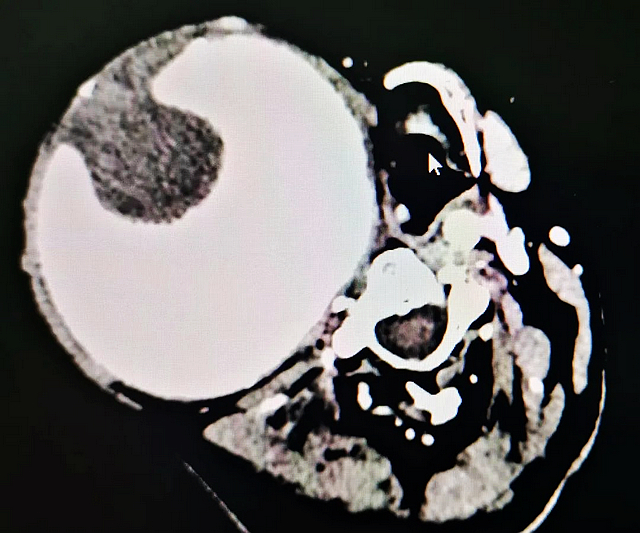

不久前,李大爷经人介绍慕名来到西南医科大学附属医院血管外科门诊,经头颈部CT血管显像,提示李大爷危急值极高,立即收入住院部做进一步处理。

“患者诊断为颈内动脉瘤,因颈内动脉瘤本身并不多见,而19年炼成如此巨大的颈内动脉瘤,我是平生第一次见到,在业界也非常罕见。”初见李大爷,见多识广的血管外科主任刘勇主任医师也惊讶不已。

据刘勇介绍,结合李大爷的具体情况,除了面临颈内动脉瘤破裂的风险,经CT检查发现其血液内还有大块血栓,血栓脱落进入颅内可能形成脑梗,另外巨大的动脉瘤压迫已导致其呼吸受阻,睡眠时鼾声如雷。

这三大危险信号,提示李大爷的颈内动脉瘤处理迫在眉睫。因颈内动脉两端分别与颈总动脉和大脑相连,其远端直达颅内,而李大爷经CT和造影检查,其颈内动脉血管远端无法显像,具体情况不明,一旦操作不慎,便可能导致脑梗或死亡,手术风险进一步增加,这也是周边很多医院不敢“开刀”的重要原因。

经测量其切除的颈内动脉瘤瘤壁直径达到11CM,而一般正常人的颈内动脉直径仅5MM左右,异常增大了20多倍,相当于一个柚子的大小。